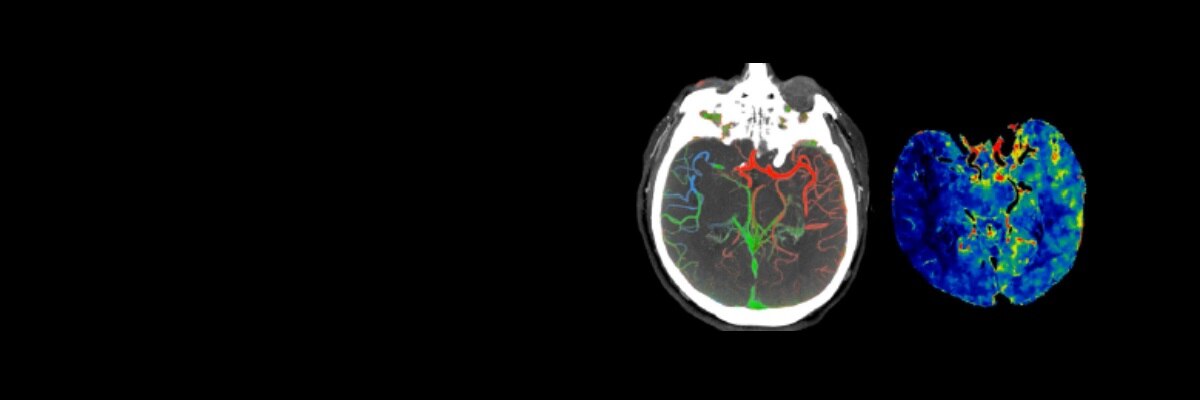

SOLUCIONES PARA ACCIDENTES CEREBROVASCULARES